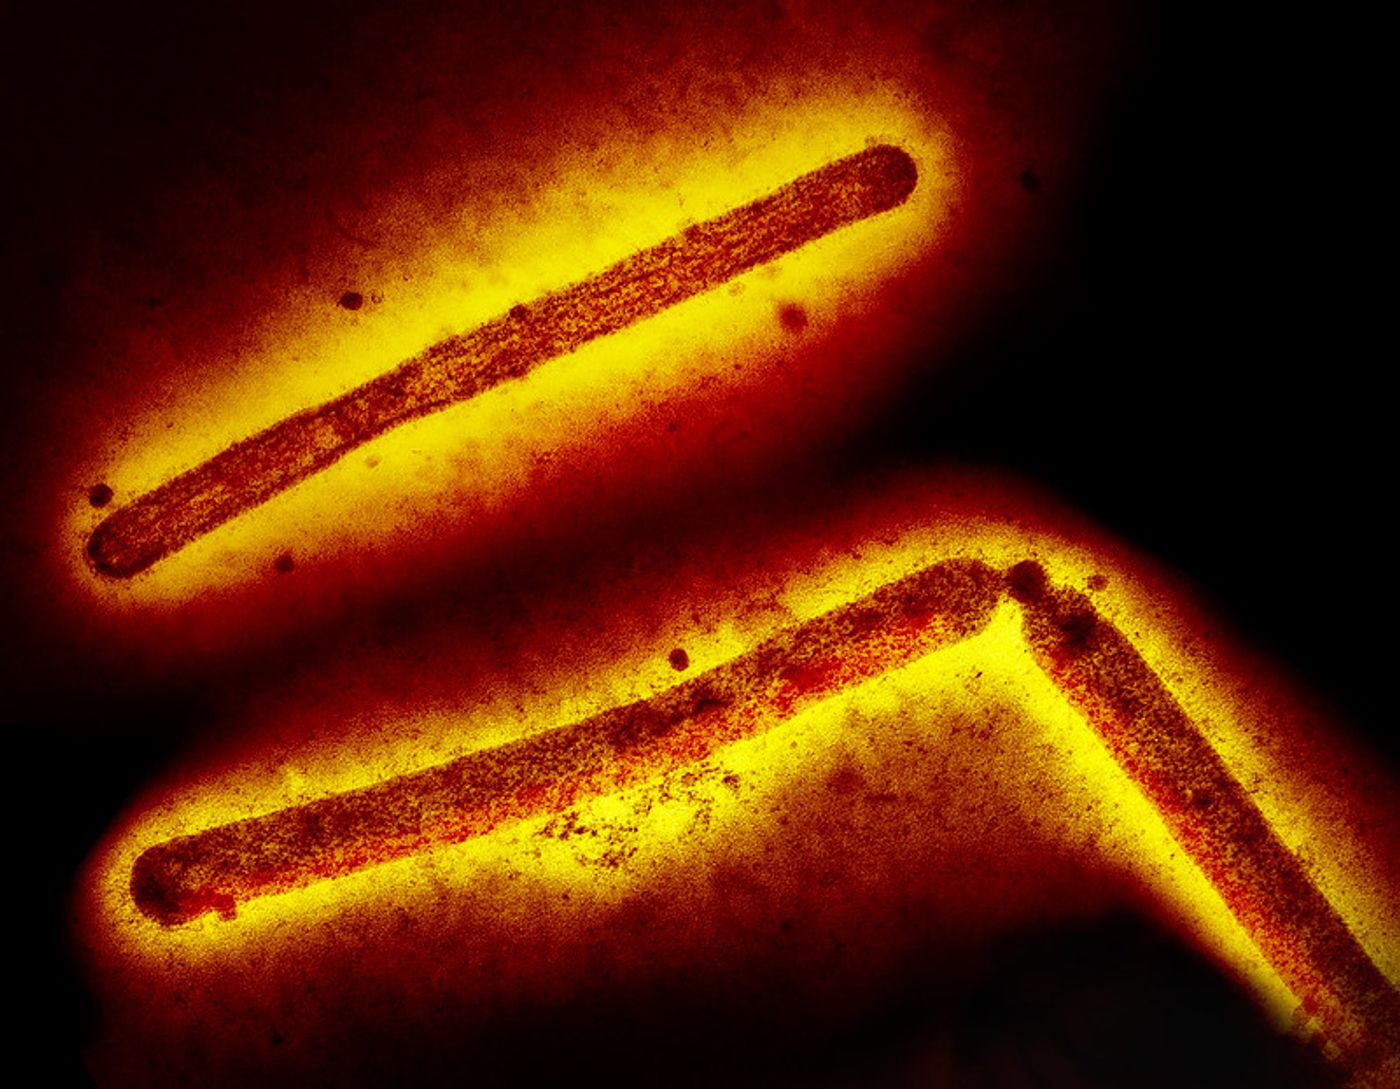

Three influenza A (H5N1/bird flu) virus particles (rod-shaped). Note: Layout incorporates two CDC transmission electron micrographs that have been inverted, repositioned, and colorized by NIAID. Scale has been modified. Credit: CDC and NIAID